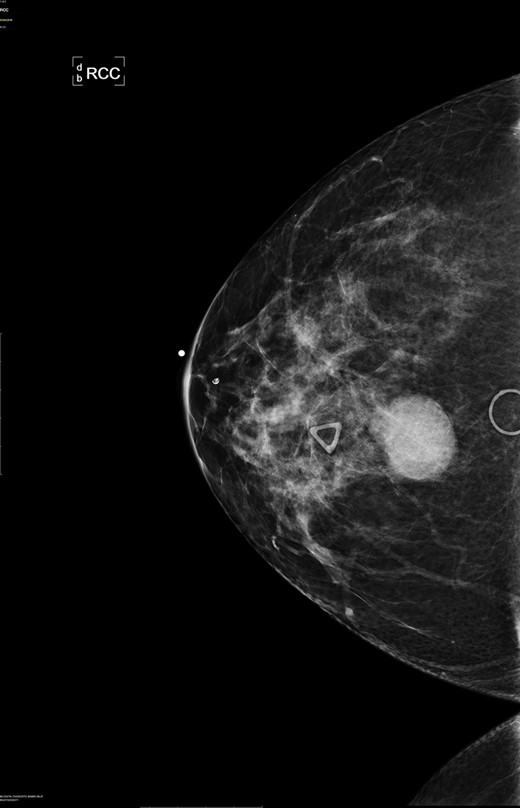

A diagnostic mammogram and ultrasound were performed to evaluate the right breast mass. The right breast imaging was categorized as BIRADS 5 (Figs 1–3). The patient underwent a right breast ultrasound-guided vacuum core biopsy of the mass and a fine needle aspiration (FNA) of the enlarged lymph node in the right axilla. Pathology of the core biopsy revealed poorly differentiated squamous cell carcinoma with tumor necrosis and calcification (Figs 4 and 5). Cytology of the right axillary lymph node was negative for metastatic carcinoma.

Right breast cranio-caudal and mediolateral oblique mammographic views, demonstrate a smooth, well rounded, mammographic density, corresponding to the palpable right breast mass. In addition, a prominent right axillary lymph node is noted in the mediolateral oblique view.